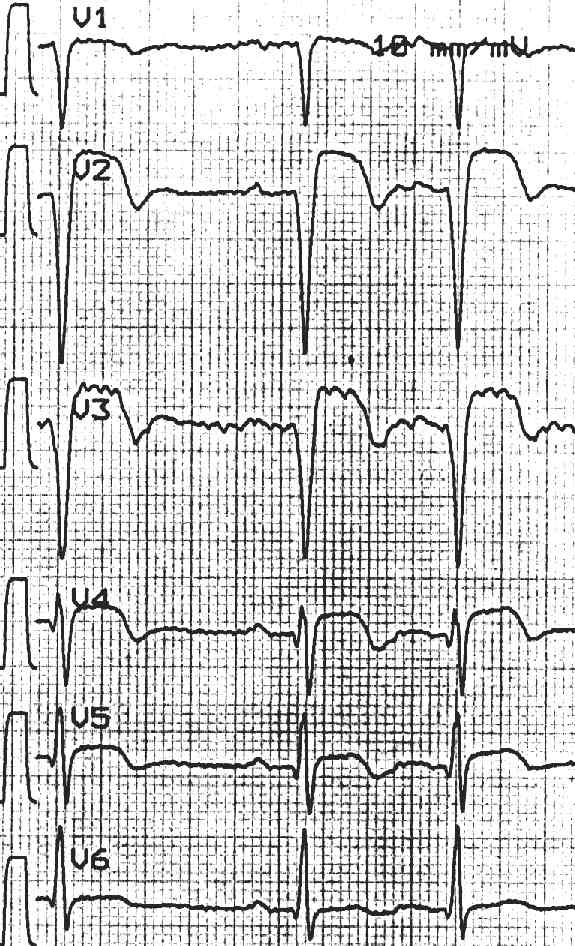

Beispiel 15: Subakuter Vorderwandinfarkt

66 - jähriger Patient mit vernichtendem Thoraxschmerz als Erstereignis.

Normocarder Sinusrhythmus, Linkslage, no. Erregungsbildung, AV-Block I°, schulterförmige ST- Streckenhebungen von V1 - V5 im Rahmen eines akuten Vorderwandinfarktes.